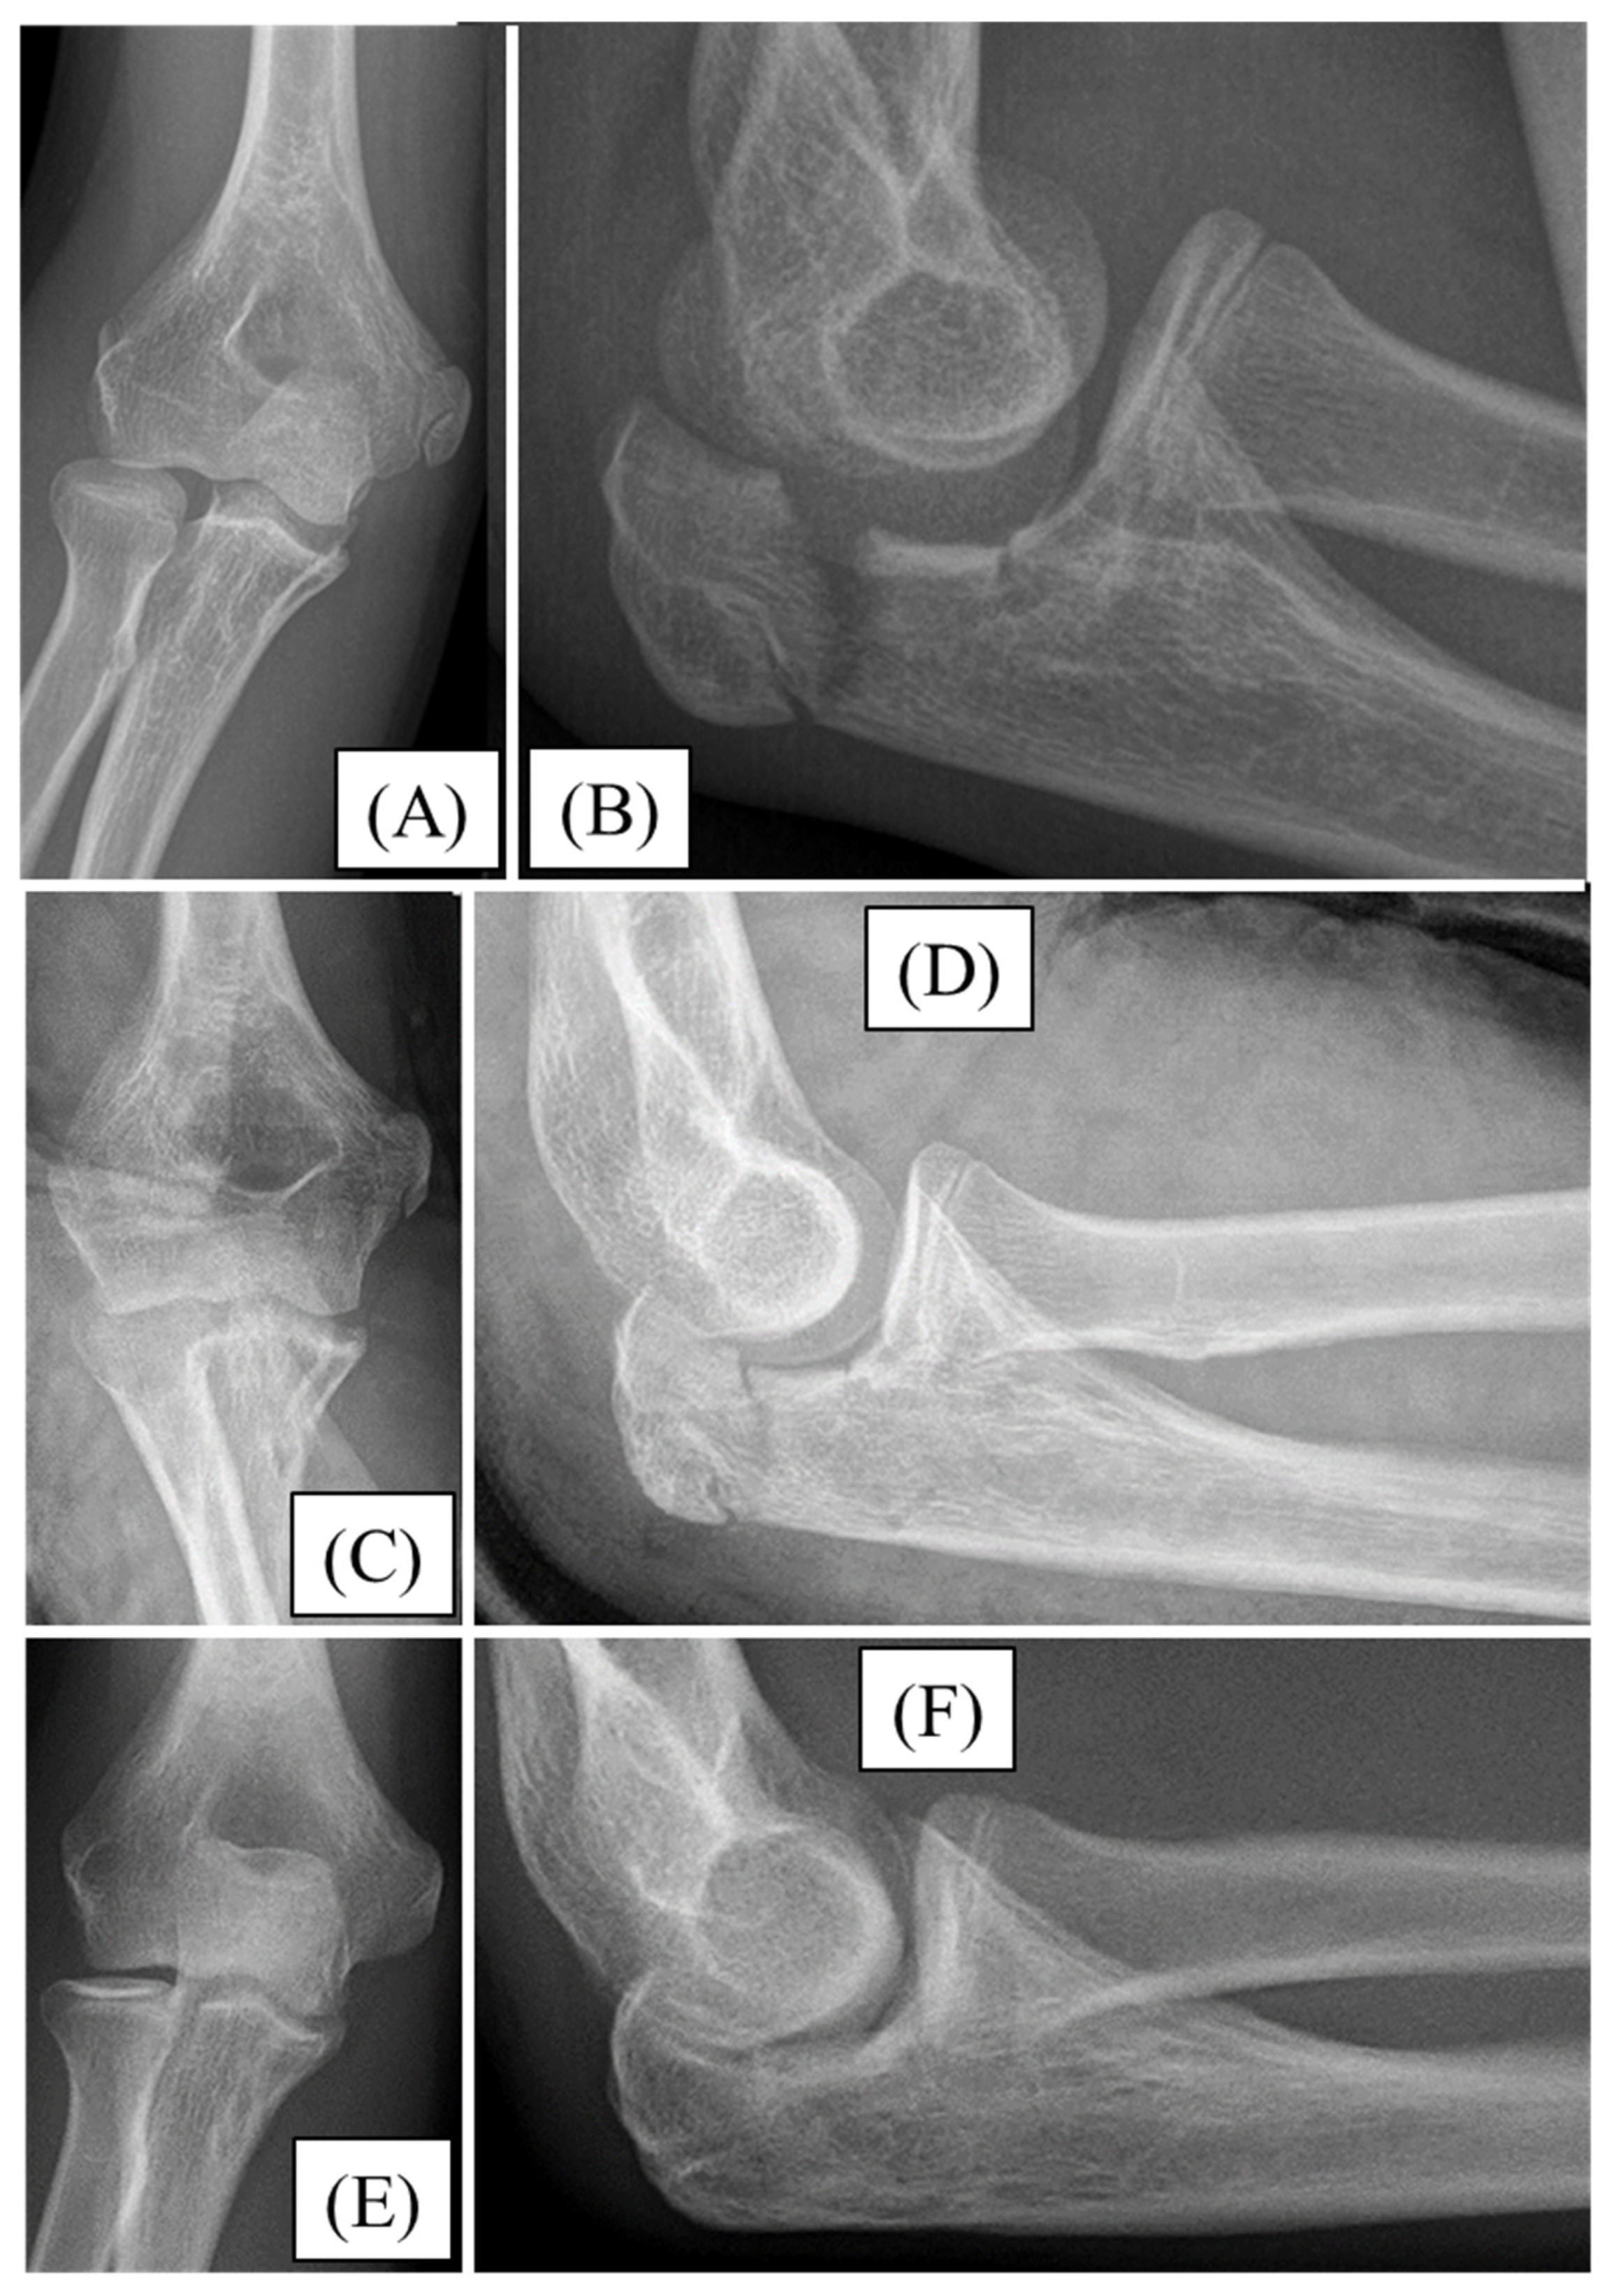

3.1. Case 1

3.2. Case 2

3.3. Case 3